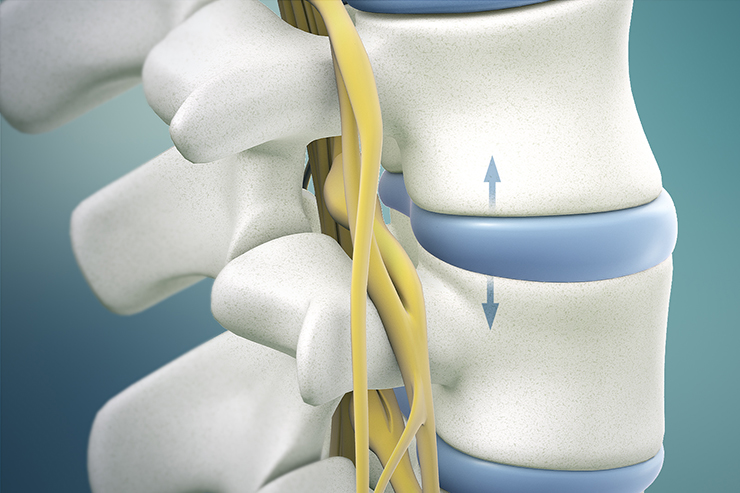

Spine decompression relieves nerve pressure, reduces back pain, and restores mobility by treating herniated discs or spinal stenosis effectively....